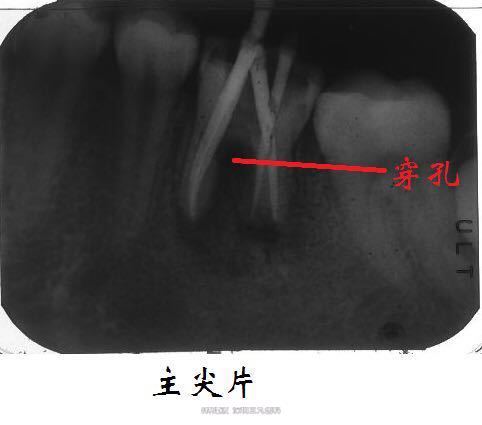

MTA修补根管穿孔一例

诊断:36根管壁穿孔、慢性根尖周炎 处理:36根管治疗,MTA修补近中根管壁。

术后第四年和第五年回访。